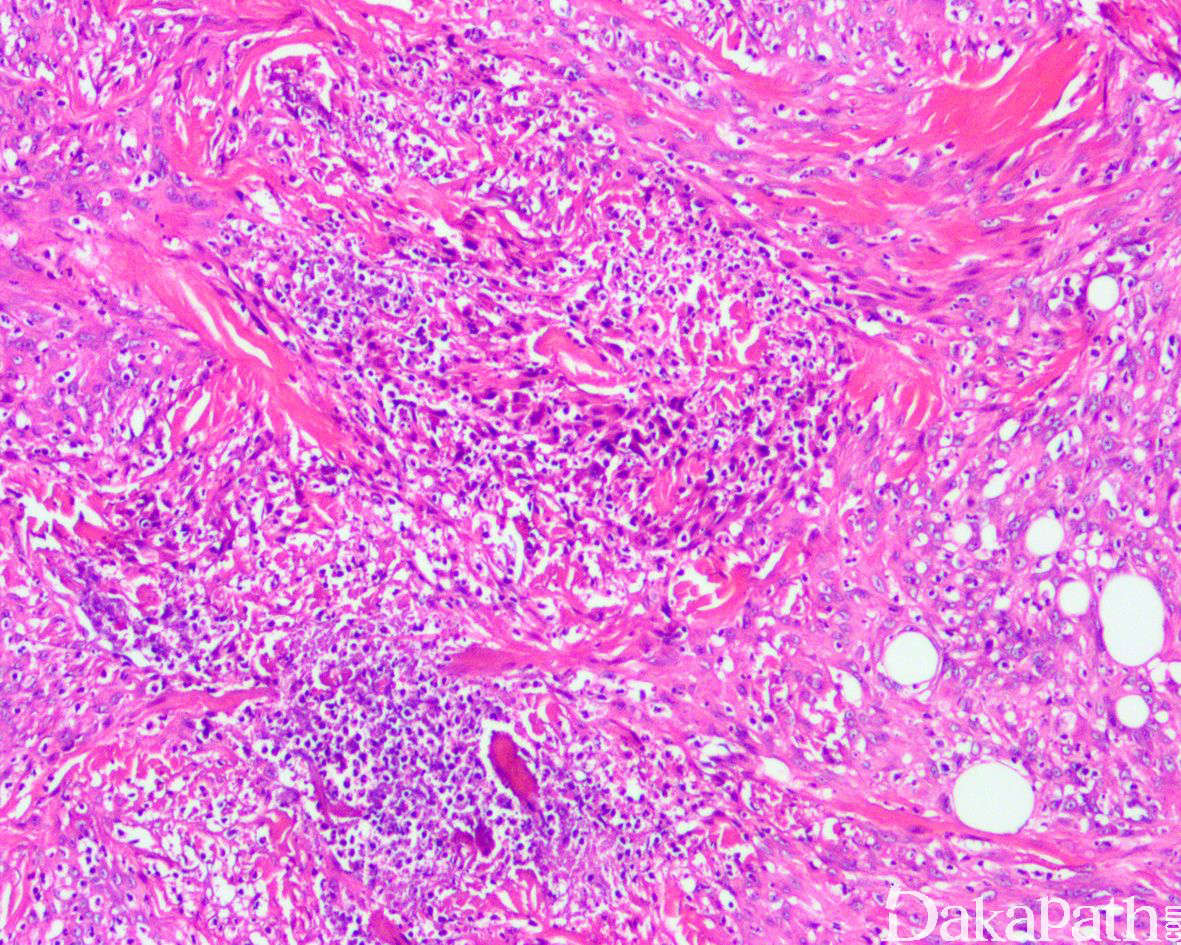

2. 多见于下肢,上肢、躯干、头部较少见; 3.66%多灶发生,累及多个组织平面(从真皮层到骨均可累及),平均直径约 1.9cm;肿瘤呈灰白结节状或界限不清的肿块,有时可伴坏死,累及皮肤时可伴溃疡;

3. 肿瘤细胞呈密集片状或不规则束状或丛状排列浸润至皮下脂肪组织和肌肉组织内;

9. 背景中可见弥漫散在的中性粒细胞浸润,极少数可见液化性坏死,通常无上皮样肉瘤可见的地图状肿瘤性坏死;